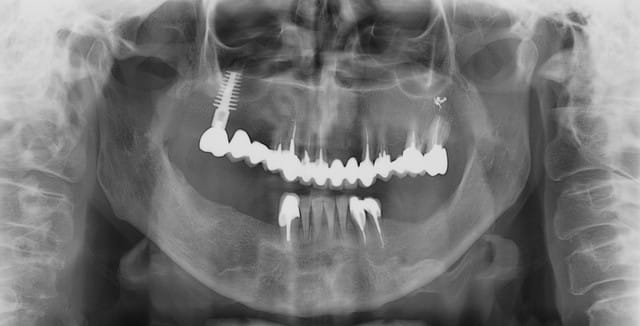

voili, voila...

avant de faire la tomosynthèse je comprenais pas pourquoi j'avais aussi peu de contraste.

le patient ne souhaite pas, ou ne peut pas se faire poser 6 implants en haut, donc...overdenture sur 4. (si possible)

4 mini implants de prévues en bas...